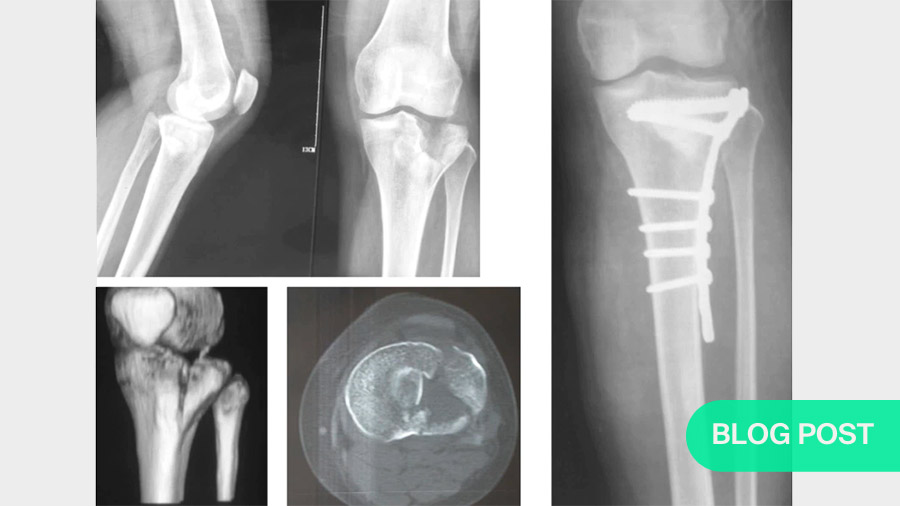

The first step is to use medical imaging to examine and classify the injury. For example, using the AO/OTA classification, considering that we’re focusing on complex fractures here, we are looking at B- or C-class fractures. Of these, the first complex classification would be a B3, with a split articular fracture and a plateau depression; the highest level of complexity—a C3—would involve fractures of two or more columns and multiple fragments or even comminution. The corresponding Schatzker classifications would be 2, 4, 5 or 6. Both the Schatzker and the AO/OTA classification systems have recently been upgraded to four-column conceptualizations. I.e., what was previously simply described as the posterior column is now divided into the posteromedial and the posterolateral columns.

Both the AO/OTA and the Schatzker classification systems are still useful. However, both are built around two-dimensional views. The more recent CT-based 3D construct classification method, which inlvolves the use of specialized software to reconstruct CT scan slices into virtual 3-dimensional models, allows a clearer, brighter view of the fracture site. This is valuable not only for choosing the optimal fixation and instrumentation, but also for deciding on the approach that will allow the most efficient access to the affected areas.

Adding 3-D reconstructions of CAT or MRI images

To include the advantages of current imaging possibilities and computing power, a range of software solutions—some of them free and open-source—are available to convert slicing scans into three-dimensional virtual models. For study or demonstration purposes, the virtual models can even be 3D-printed in very little time. Most importantly, allowing us to view the injury site from all angles offers major advantages not only for deciding on our implantation and reduction strategies, but also on the finer details of access and patient positioning. By minimizing the time the patient is under anaesthesia, this also reduces the chances of complications.